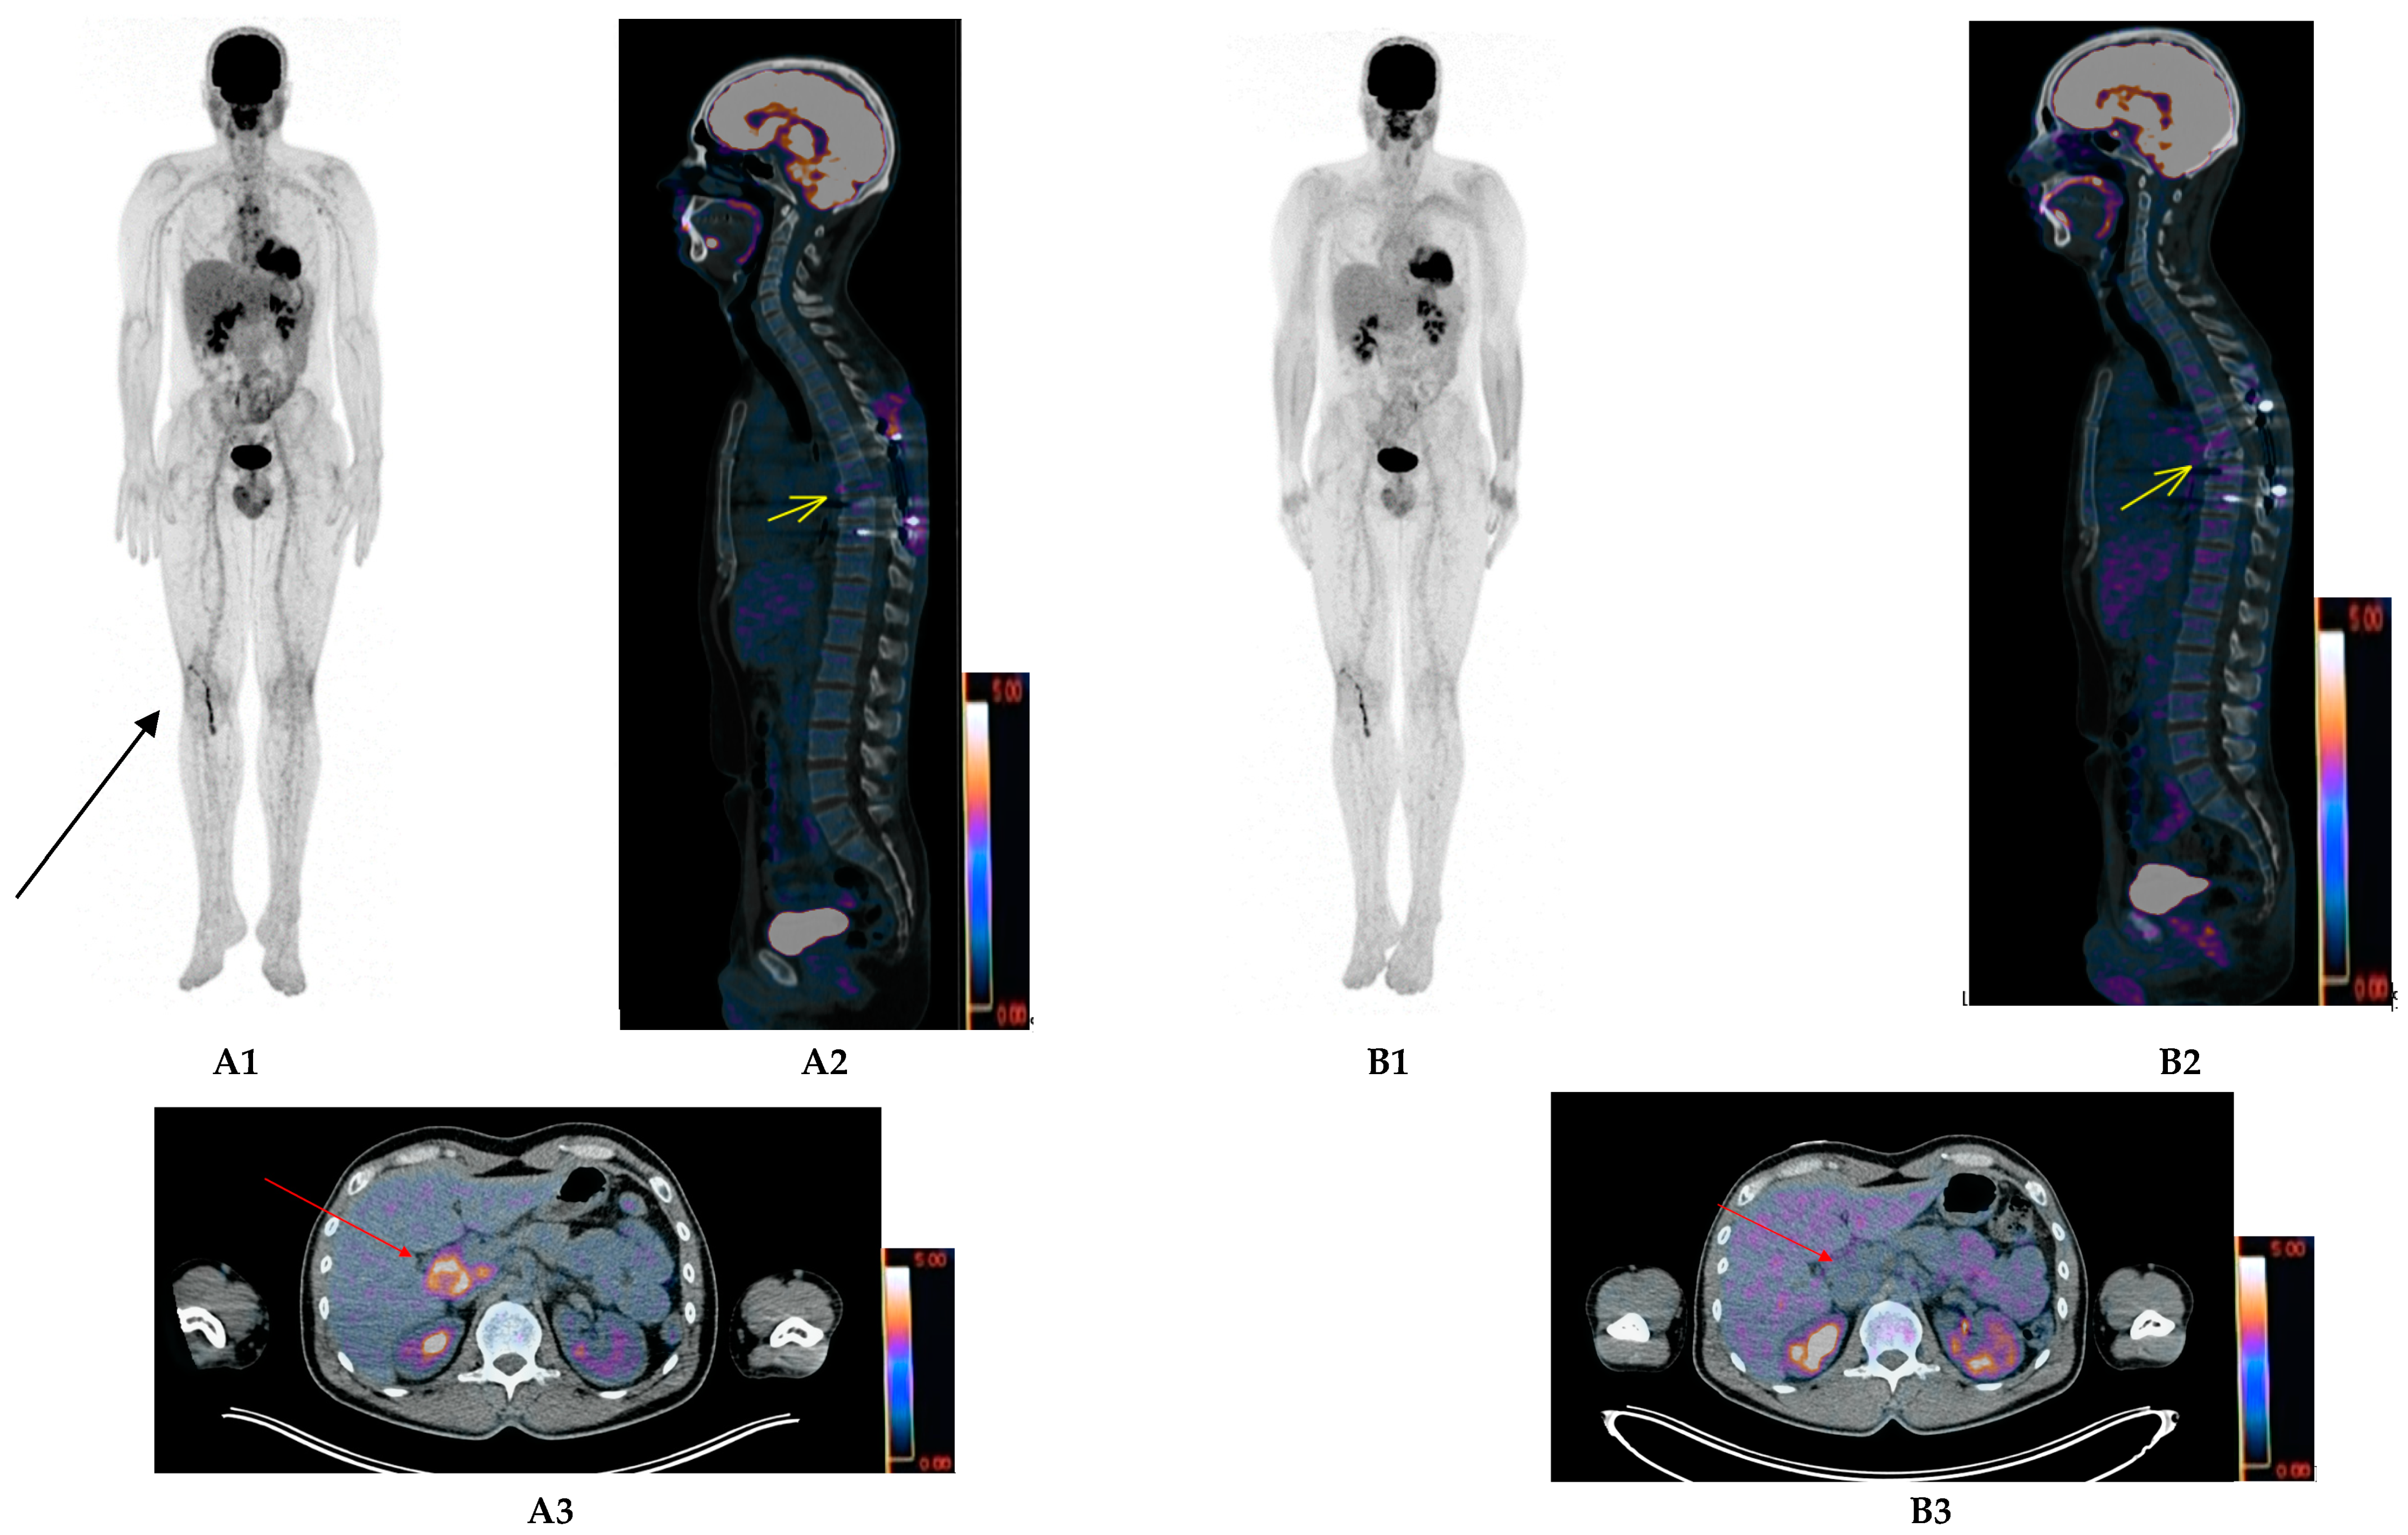

- Pan, Q.; Cao, X.; Luo, Y.; Li, J.; Feng, J.; Li, F. Chemokine receptor-4 targeted PET/CT with 68Ga-Pentixafor in assessment of newly diagnosed multiple myeloma: Comparison to 18F-FDG PET/CT. Eur. J. Nucl. Med. Mol. Imaging 2019, 47, 537–546. [Google Scholar] [CrossRef]

- Rasche, L.; Alapat, D.; Kumar, M.; Gershner, G.; McDonald, J.; Wardell, C.P.; Samant, R.; van Hemert, R.; Epstein, J.; Williams, A.F.; et al. Combination of flow cytometry and functional imaging for monitoring of residual disease in myeloma. Leukemia 2019, 33, 1713–1722. [Google Scholar] [CrossRef] [PubMed]